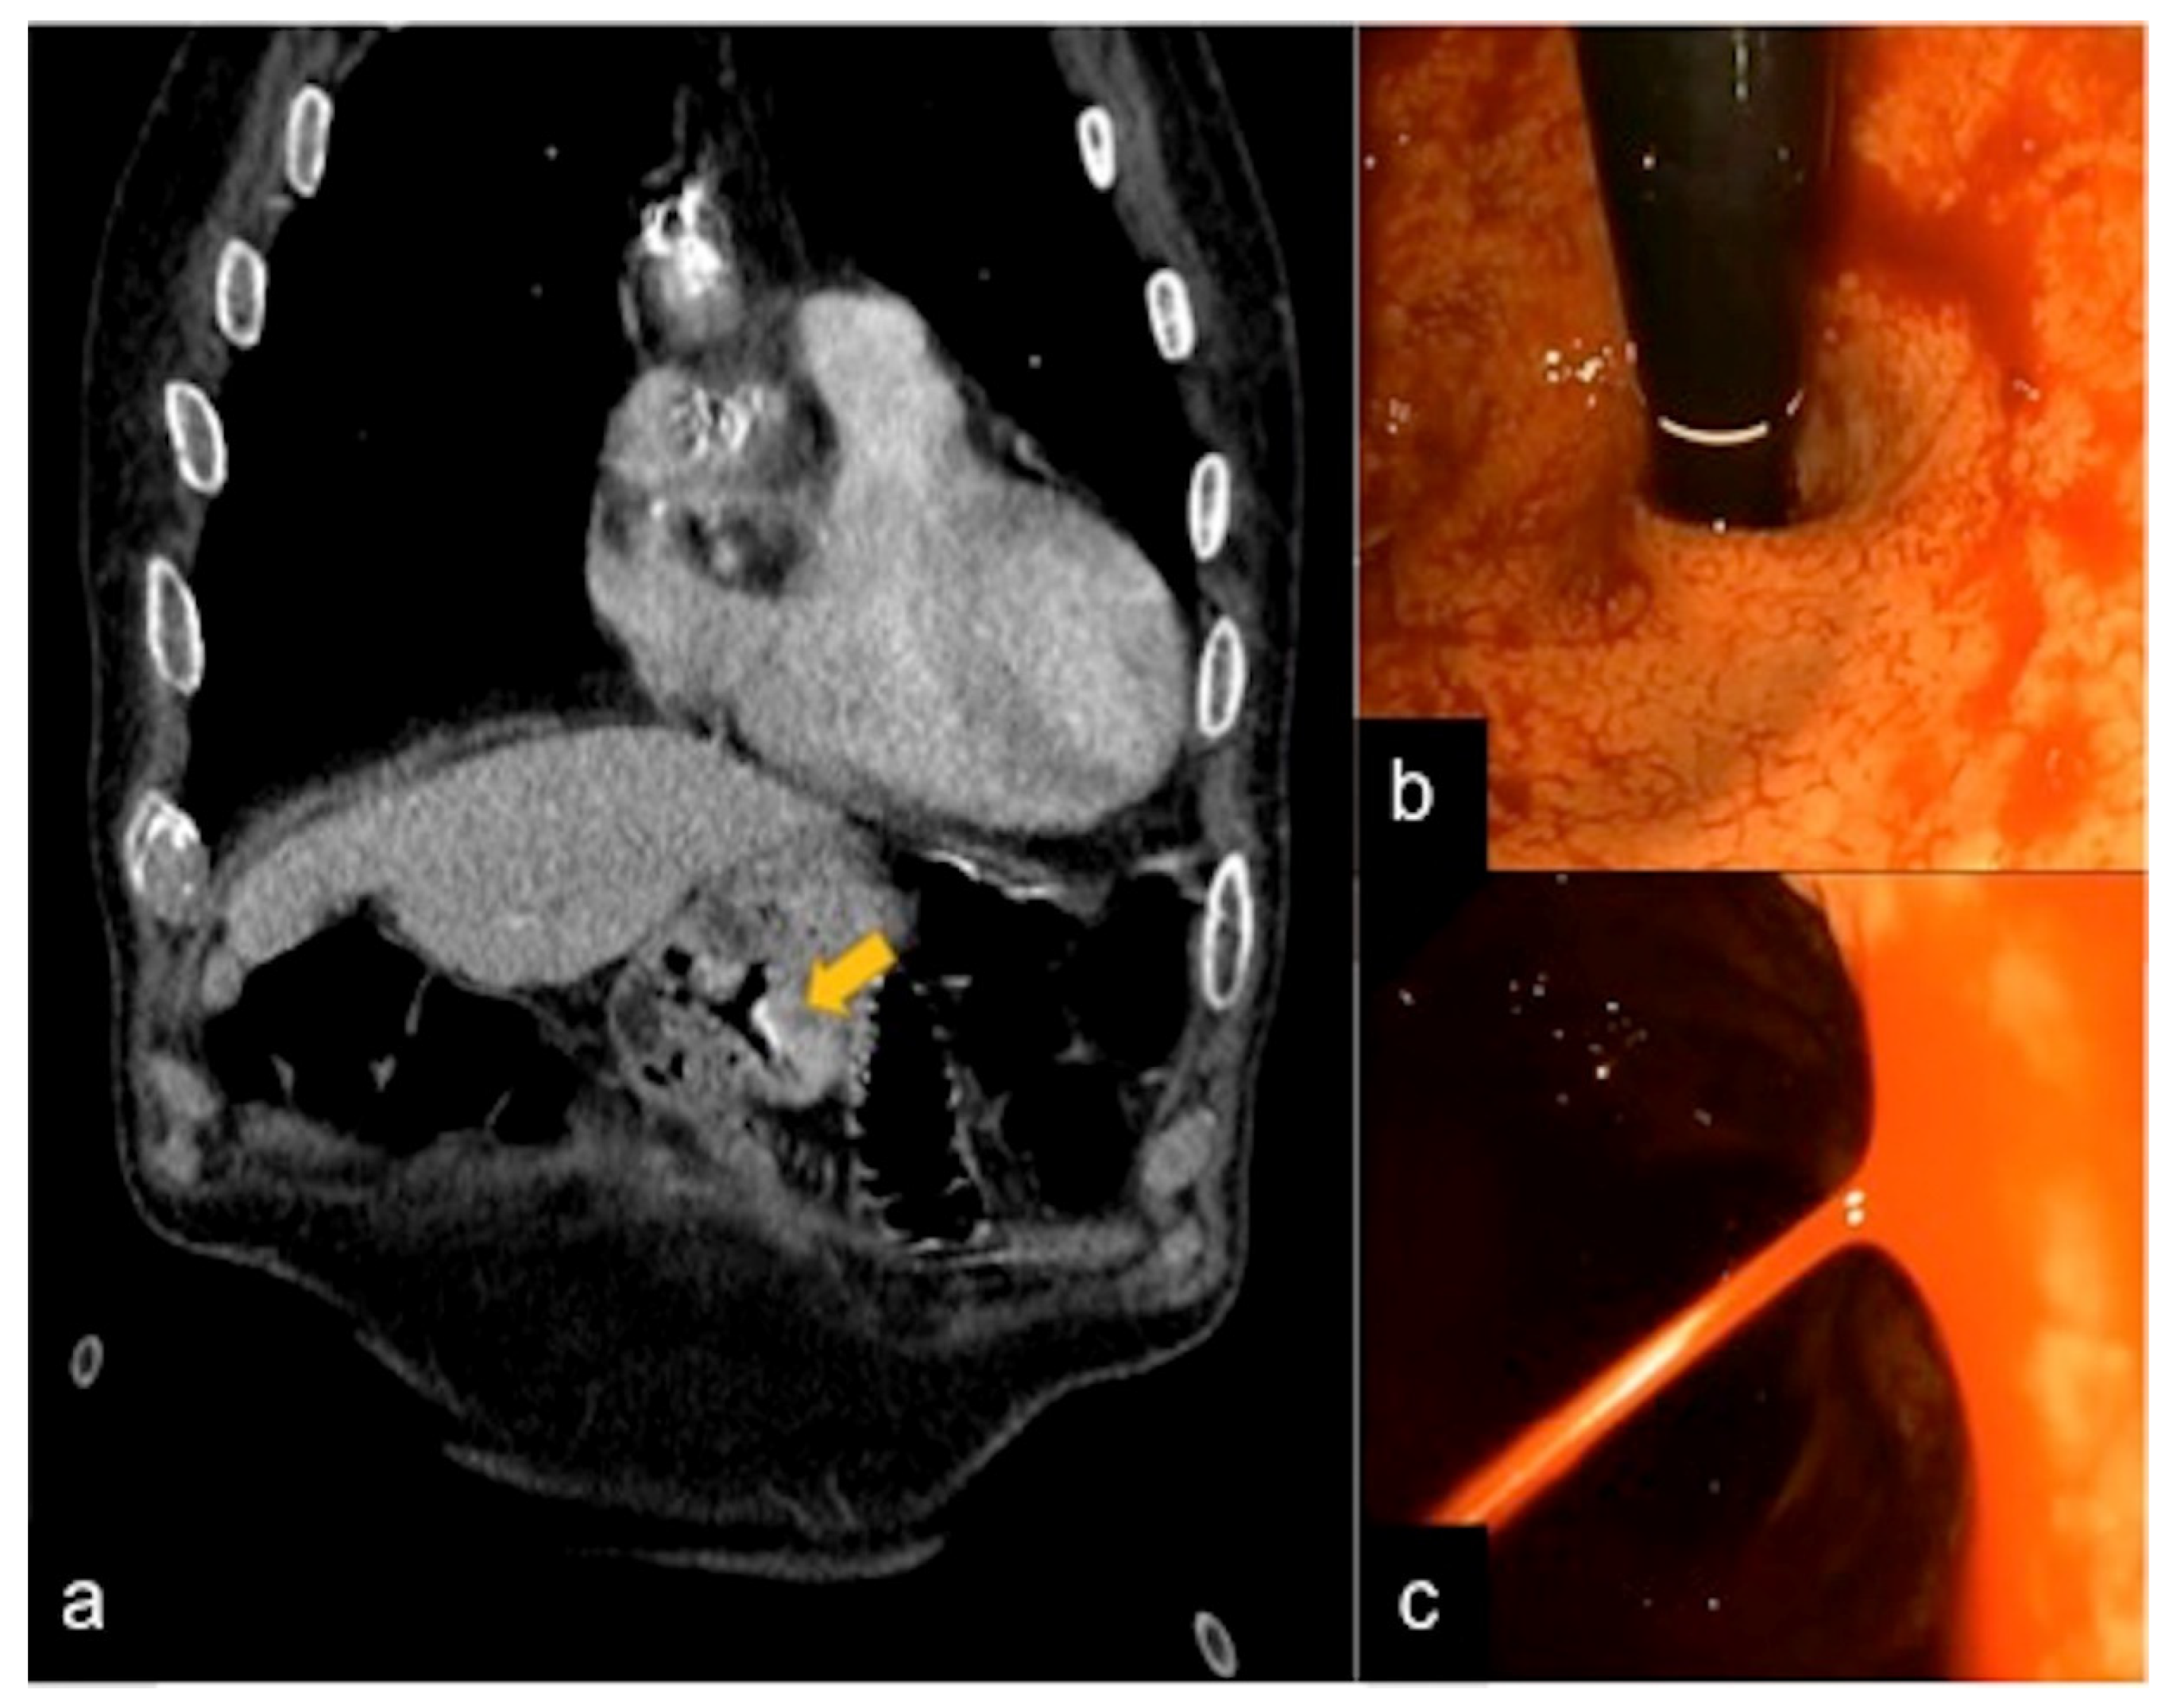

| Aorto-Gastric Fistula (Figure 28) | Copious bleeding. | A connection between the aorta and the gastric lumen. Absence of adipose cleavage planes. |

- Martino, A.; Bennato, R.; Oliva, G.; Pontarelli, A.; Picascia, D.; Romano, L.; Lombardi, G. Primary aortogastric fistula: An extraordinary rare endoscopic finding in the setting of upper gastrointestinal bleeding. Endoscopy 2021, 53, E60–E61. [Google Scholar] [CrossRef]